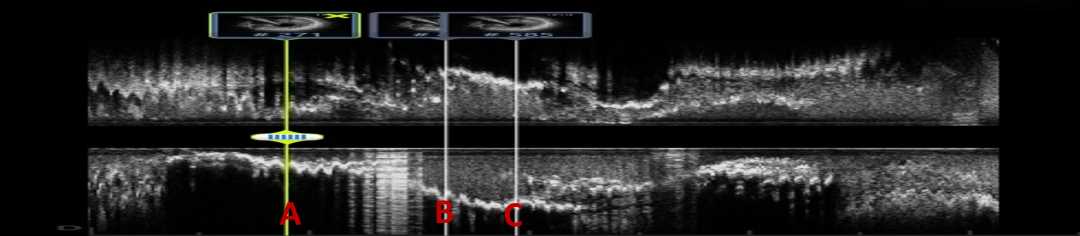

IVUS实时定位寻找开口

LAD开口不明确,送入IVUS至D1手动回撤,实时寻找LAD开口方向

IVUS回撤过程中可借助血管直径的变化判断闭塞段入口位置,在主支和分支血管汇合段,主支血管管腔在影像下会显示为突然扩张,附近多半可以发现IVUS图像在某个方向上有闭塞主支血管的影像。

分支血管的IVUS回撤过程中,还可通过闭塞血管的影像表现判断主支与分支的夹角大小,从而指导CTO导丝的塑形:汇入点以远回拉时可见多幅闭塞血管影像,这往往意味着分支血管和主支血管夹角比较小;相反,只能在闭塞部位见到主支血管,以远均未发现闭塞血管,则意味着主支血管和分支开口角度很大,从而辅助判断导丝塑形,提高近端纤维帽穿刺的成功率。

复查IVUS可见:LAD多处环形钙化,原支架贴壁不良,支架远端导丝走形在支架外,IVUS指导下重新调整导丝进入支架

经后扩复查IVUS

-

LAD中远段支架贴壁良好,LAD开口显示有明显支架贴壁不良

LAD近端EEM直径4.74mm,送入4.5*15 NC进行后扩

PCI术后IVUS

IVUS提示:后扩张处理后支架膨胀、贴壁良好